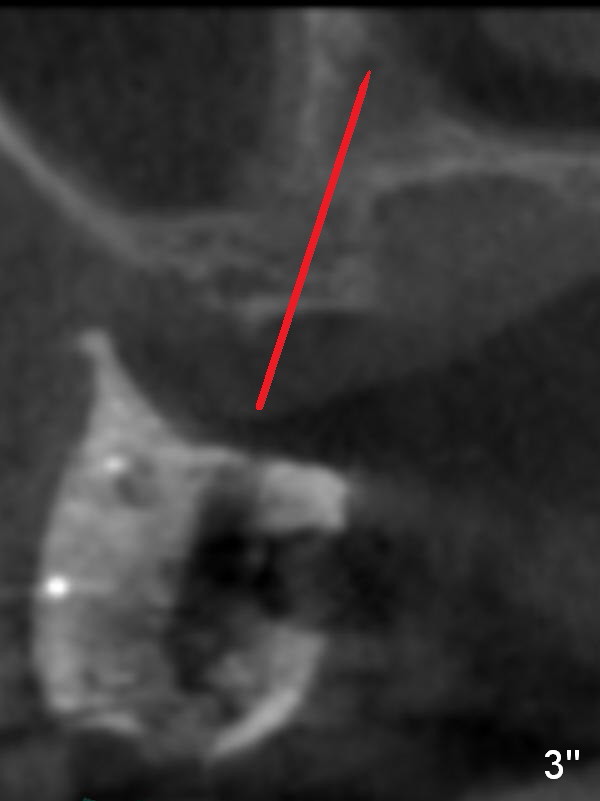

Since it is narrow, it should be expanded prior to implant placement. A small pilot drill, 1.2 or 1.6 mm in diameter, is used to initiate bone expansion (Fig.3'' red line).